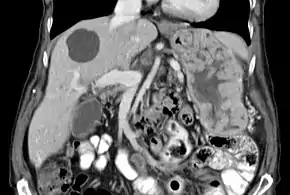

| Biopsy of the stomach in Ménétrier disease showing the substantial pit hyperplasia makes the large rugal folds appear to be covered by myriad polyps resembling hyperplastic polyps. The muscularis propria is the folded structure at the bottom center. | |